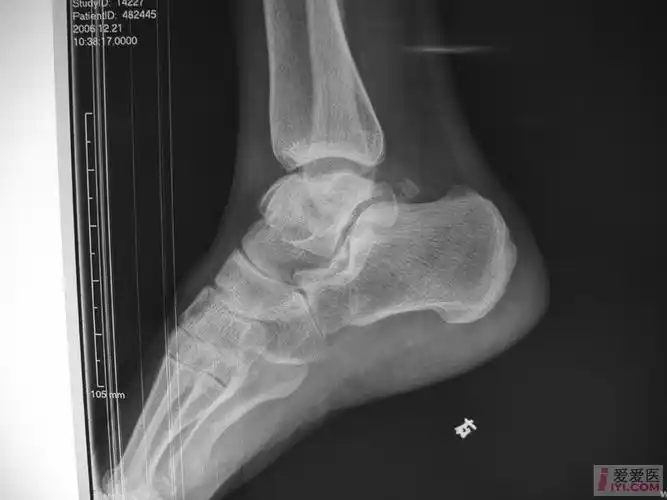

左脚跟粉碎性骨折